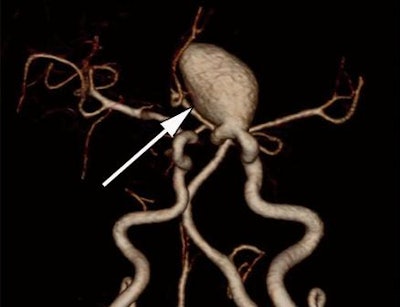

As a result, the group sought to determine if subtracted 320-detector-row volumetric CTA, which offers bone-free visualization of aneurysms, could accurately detect cerebral aneurysms.

The subtracted CTA volumetric data were gathered by subtracting the mask image volumetric data from the conventional nonsubtracted CTA volumetric data using the console's software. Bone-tissue data were automatically removed, and the resulting data were reviewed on a Voxar workstation (Toshiba) for 3D visualization using direct volume-rendering techniques or maximum-intensity projections.

"The accuracy of nonsubtracted volumetric CT angiography was lower than that for subtracted volumetric CT angiography, especially for aneurysms adjacent to bone tissue," the authors wrote.

"The aneurysms missed at nonsubtracted volumetric CT angiography were generally located in the internal carotid artery," they wrote. "Detection of cerebral aneurysms adjacent to bone tissue was still challenging at nonsubtracted volumetric CT angiography because of the presence of overlying bone structures."

Subtracted volumetric CTA also had its limitations: The two missed cerebral aneurysms on subtracted volumetric CTA were microaneurysms, which the technique generally struggled to identify. The technique also does not display atherosclerotic plaque and aneurysmal calcification, and it could not present the relationship of aneurysms to bone structures, according to the group.